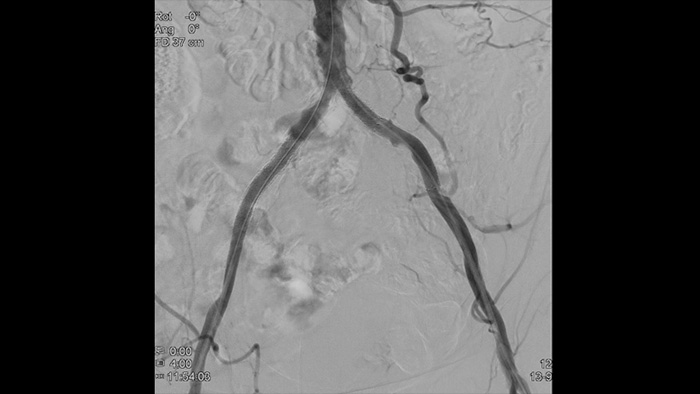

Our Vascular suite provides workflow options, dedicated interventional tools, and a broad selection of advanced vascular devices to improve procedural efficiency and redefine outcomes for your patients with aortic disease. They support each step of your procedure – as you decide, guide, treat and confirm treatment results.

VesselNavigator provides an intuitive and continuous 3D roadmap based on existing CTA and MRA datasets to guide you through vasculature during aortic procedures. One study1 showed an average of 170 ml contrast reduction during endovascular repair of complex aortic aneurysms with the use of VesselNavigator CTA image fusion guidance.2 Another study showed a reduction in average procedure time from 6.3 to 5.2 (1.1) hours during FEVAR/BEVAR with VesselNavigator CTA image fusion guidance.3

With Philips Azurion a breakthrough in workflow improvement has been realised, resulting in proven efficiency. With the ever growing number of patients with aortic disease, Azurion offers a number of workflow innovations designed to help vascular teams work efficiently and consistently, while maintaining a single-minded focus on the patient and managing radiation dose during interventions.